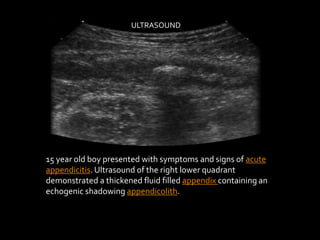

15 year old boy presented with symptoms and signs of acute

appendicitis. Ultrasound of the right lower quadrant

demonstrated a thickened fluid filled appendix containing an

echogenic shadowing appendicolith.